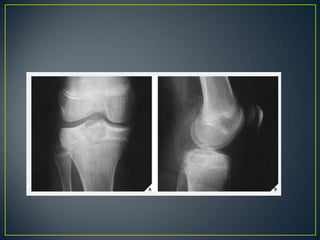

• The type of bone destruction caused by a tumor is

primarily related to the tumor growth rate.

• Not pathognomonic for any specific neoplasm.

• Geographic.

• Moth Eaten.

• Permeative.

• Categorized as uninterrupted or interrupted .

• The first type of reaction is marked by solid layers of

periosteal density, indicating a long-standing benign

process.

• Also seen in nonneoplastic processes such as

Langerhans cell histiocytosis, osteomyelitis, bone

abscess or in fractures in the healing stage.

• The interrupted type of periosteal reaction suggests

malignancy or a highly aggressive nonmalignant process

and may present as a sunburst pattern, a lamellated

(onion-skin) pattern, a velvet pattern, or a Codman

triangle.